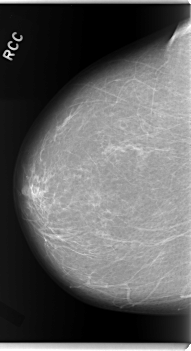

C_0114_1.RIGHT_CC

RIGHT_CC LINES 5952 PIXELS_PER_LINE 3232 BITS_PER_PIXEL 12 RESOLUTION 50 NON_OVERLAY

FILE: C_0114_1.LEFT_CC.OVERLAY

TOTAL_ABNORMALITIES 1

ABNORMALITY 1

LESION_TYPE MASS SHAPE IRREGULAR MARGINS MICROLOBULATED

ASSESSMENT 5

SUBTLETY 5

PATHOLOGY MALIGNANT

TOTAL_OUTLINES 1

BOUNDARY